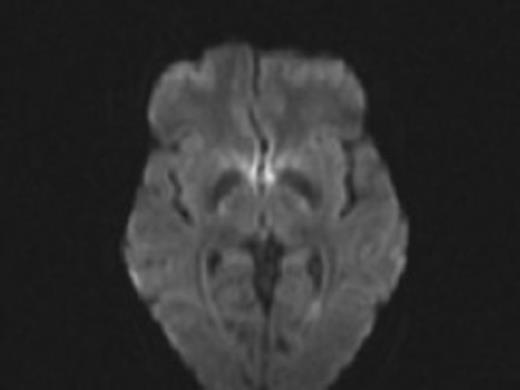

Thereafter, her ventricles diminished in size back to their baselines and her neurological exam slowly improved back to her baseline over the course of 2 months. She had no lesions noted in the opercular regions on her MRI post operatively (Fig. 4).